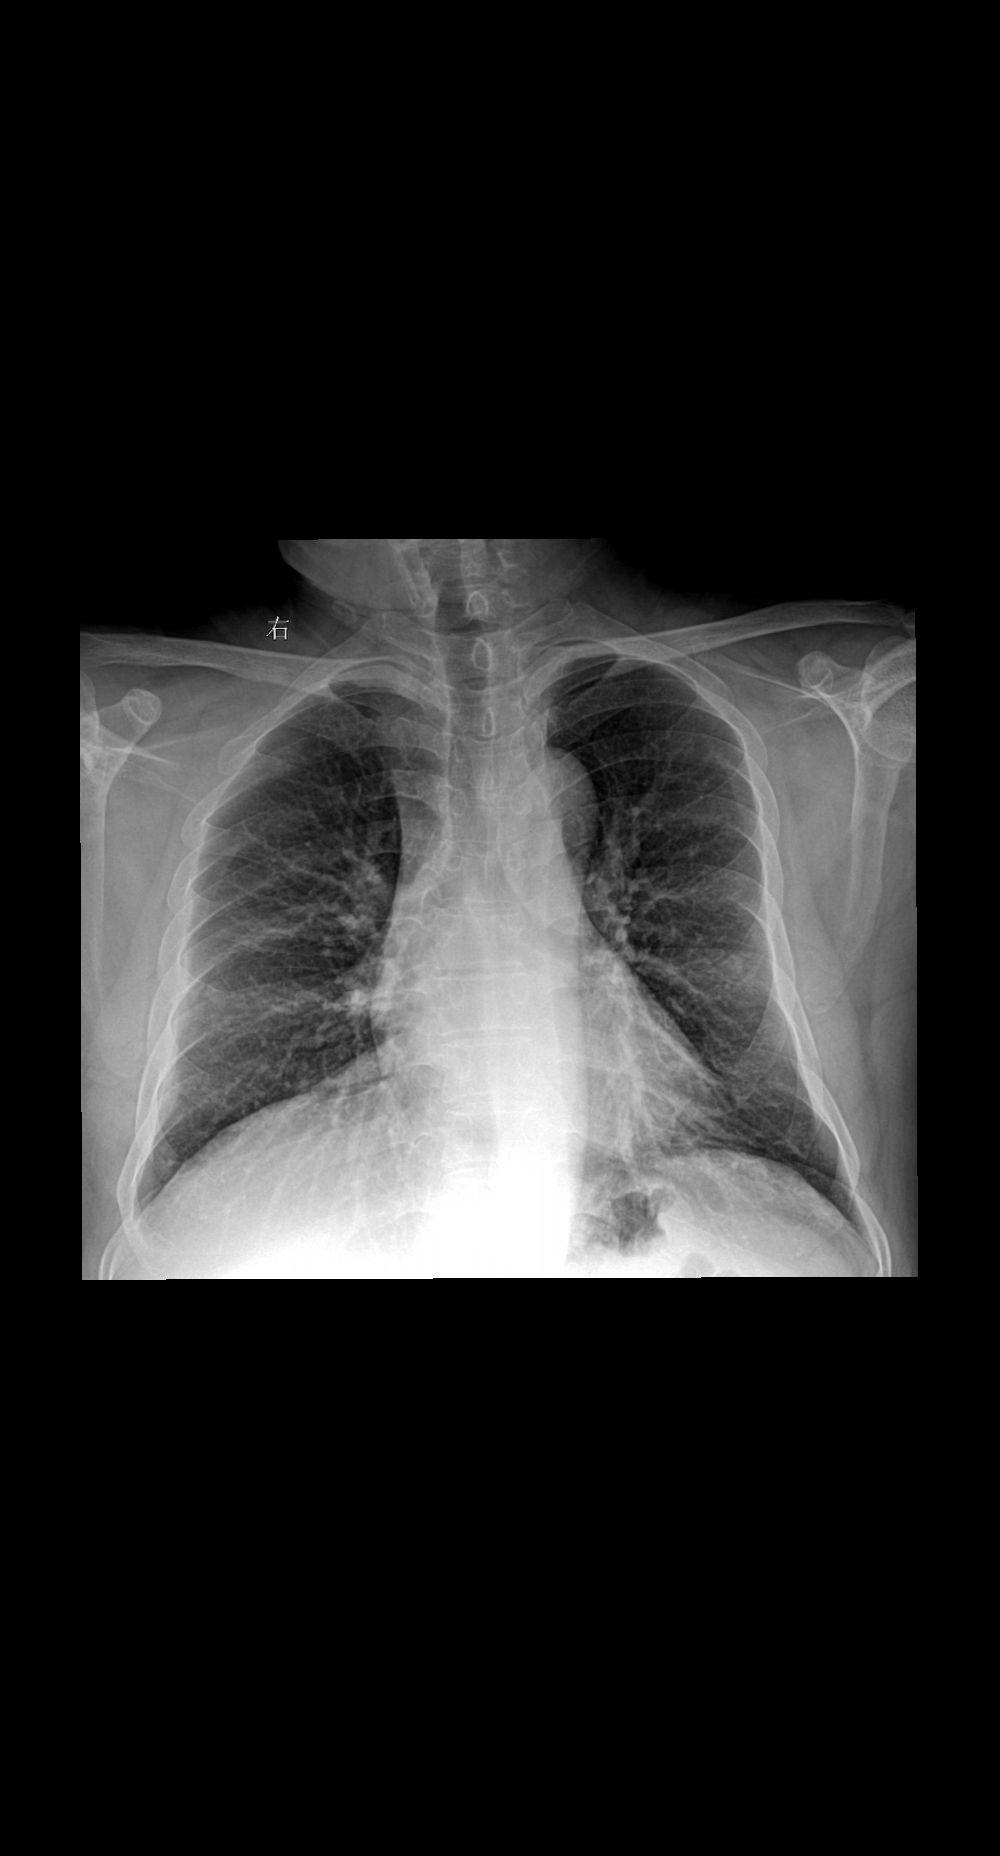

家人们你们拍胸片的时候让患者深呼吸憋气吗 患者主诉咳嗽感冒一周29岁女